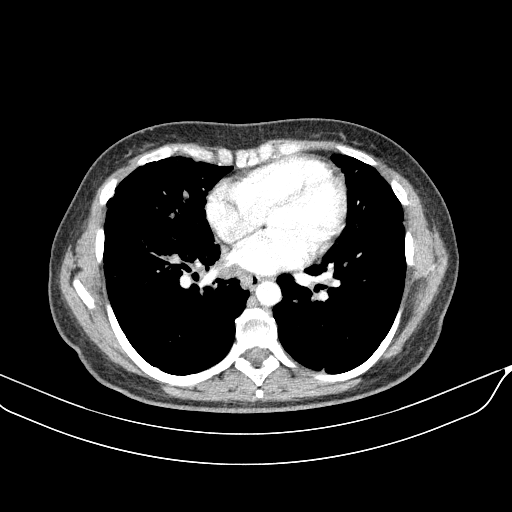

Image Grid

4Γ—3 grid: Rows show different image types (Original NATIVE, Reconstructed NATIVE, Original VENOUS, Generated VENOUS), Columns show windowing techniques (No Window, Lung Window, Mediastinum Window)

Generated VENOUS CT scan (A→B translation)

Full window (WL 1023.5, WW 4095 β†’ Low βˆ’1024, High +3071)

Lung window (WL -600, WW 1500 β†’ Low βˆ’1350, High +150)

Mediastinum window (WL 40, WW 400 β†’ Low βˆ’160, High +240)